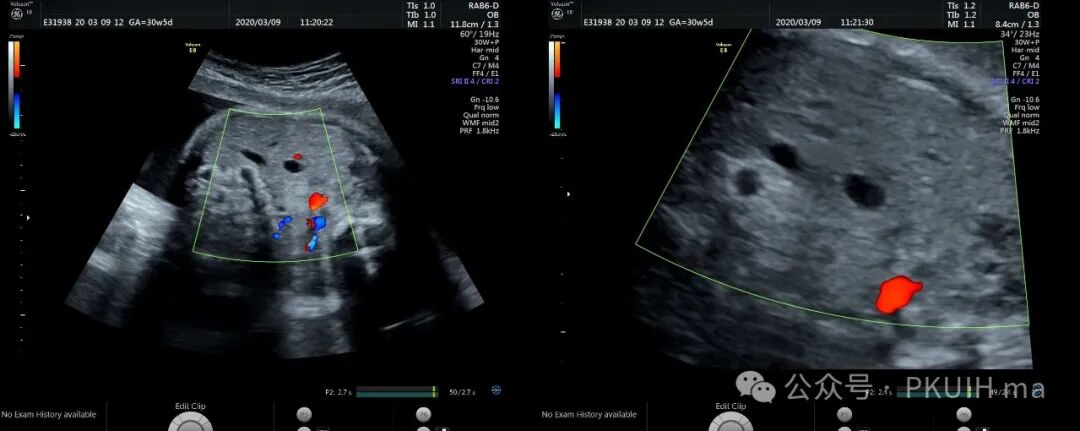

上两张图(第二张是37周)是一例在30周发现的肝囊肿,在随后观察中囊肿一直无变化